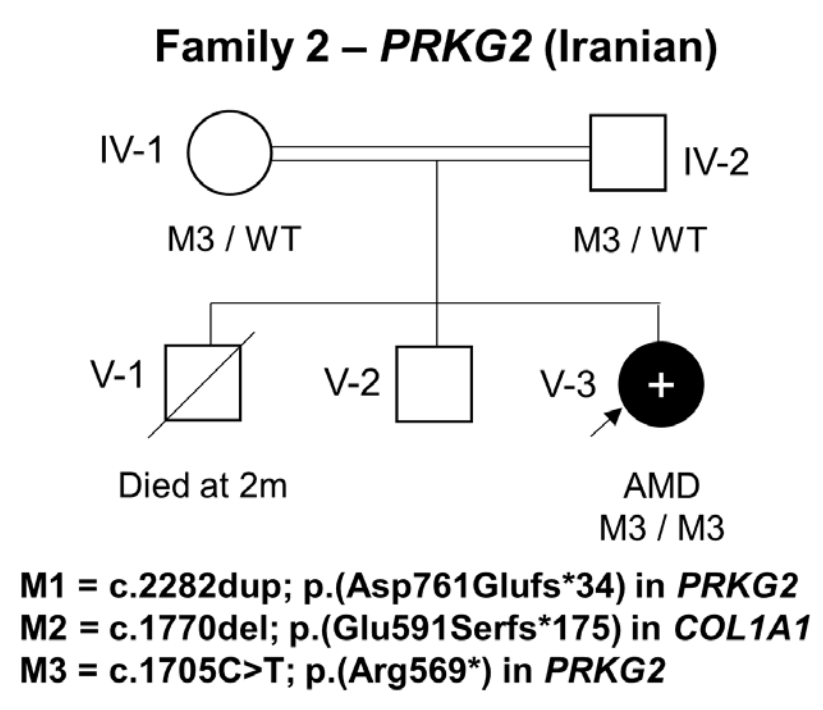

在家系2中,一个患有肢端发育不良的女孩的外显子组测序显示了一个纯合子致病变异PRKG2c.1705C>T;(Arg569*)。将F2-V-3的基因组数据与之前发表的病例进行比较,未能检测到PRKG2基因座 (Locus)上共有的单倍型。c.1705 C>T的复发似乎更有可能是由于单独的突变事件。

家系2家系分析图,女孩M3/M3突变

家系2一代测序验证,突变后翻译异常终止

这里描述的这两种变异都非常罕见,gnomAD数据库中没有p.Asp761Glufs*34,而p.Arg569*为单基因。在这两个家系中,致病变异都存在于较大的ROHs中。虽然p.Arg569*突变已经被证明影响下游的MAPK途径,但家系1中的p.Asp761Glufs*34很可能也是有害的,因为蛋白C末端Asp>Phe及33个氨基酸发生替换。在计算机建模中的研究突出了该区域的结构重要性,特别是终末Phe762残基。